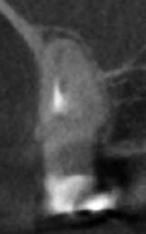

A radiológiai felvételek elemzése során a fog gyökércsúcsának megfelelően radiolucens elváltozást észleltünk, valamint a fognyak területének megfelelően szintén egy radiolucens területet figyelhettünk meg (1–2. ábra). Az elváltozások kiterjedésének és mélységének pontosabb meghatározása érdekében CBCT-felvétel készült (3. ábra). A felvétel alapján Heithersay-féle III. osztályú külső fognyaki gyökérfelszívódást diagnosztizáltunk (Heithersay Class III external cervical invasive root resorption; ECIR). Ezzel egyidejűleg pedig szimptomatikus periapikális periodontitis is fennállt. Ezt követően a pácienst a vizsgálati eredményekről, a kezelési alternatívákról és a várható prognózisról is tájékoztattuk.

A CBCT-felvételek rendkívül hasznos információkkal szolgálhatnak az endodonciai kezelések során. A felvételek segítségével meghatározhatjuk a külső fognyaki rezorptív lézió kiterjedését, felismerhetjük és osztályba sorolhatjuk az esetleges periapikális elváltozásokat, valamint nagyobb pontossággal felmérhetjük a fog belső anatómiai felépítését. Több szerző egymástól függetlenül is igazolta, hogy a CBCT rendkívül hasznos eszköz a rezorptív léziók diagnosztizálása során.

3. a–d ábra: A koronális síkú metszeten jól megfigyelhető a lézió mesio-distalis kiterjedése (a), a szaggitális síkú metszet a lézió vesztibulo-orális nagyságát mutatja (b), a gyökércsúcs körül elhelyezkedő lézió a 3 dimenziós rekonstrukciós képen és a mesio-disztális irányú metszeten is jól megfigyelhető (c–d).

A cikkekben bemutatott esetnél a kezelésre szoruló fog gyökércsúcsánál periapikális lézió volt megfigyelhető és ezzel egyidejűleg külső fognyaki gyökérrezorpció is fennállt. A periapikális és a rezorptív lézió méretének pontos meghatározását és térbeli elhelyezkedésének vizsgálatát CBCT-felvétel segítségével végeztük.

A periapikális léziók rezekciót követő gyógyulási hajlamát több faktor is befolyásolhatja. Ezek közül elsősorban a retrográd preparáció mélységét (amelynek minimum 3 mm-t el kell érnie) és a retrográd gyökértömés során felhasznált anyagot emelnénk ki. A beavatkozás óta eltelt idő is hatással van a gyógyulás aktuálisan megfigyelhető stádiumára. Minél hosszabb idő telt el a beavatkozás óta, potenciálisan annál teljesebb körű csontos telődésre számíthatunk. Ebben az esetben az obszervációs periódus során több CBCT-felvételt is készítettünk, hogy végig tudjuk követni a gyógyulás folyamatát. A kezelés során a fogat szándékosan eltávolítottuk, majd a rezorpciós üregben lévő granulációs szövetet kikürettáltuk és a megtisztított felszíneket 90%-os triklór-ecetsavval fertőtlenítettük. Az így előkészített üreget hidrofil tulajdonságokkal rendelkező dual kötésű nano-hibrid resintartalmú ionomer cementtel töltöttük fel (Geristore, DenMat; 4. ábra).

Ezt követően a gyökércsúcsot extraorálisan rezekáltuk, majd a gyökércsatornát retrográd irányból ultrahangos eszközök segítségével 3 mm mélységben feltágítottuk (EndoSuccess apikális sebészeti készlet, EndoSuccess apical surgery kit; ACTEON). A retrográd gyökértömést ásványi trioxid aggregátum (mineral trioxide aggregate, MTA) felhasználásával végeztük (CeraPutty, Meta Biomed), majd replantáltuk a fogat. A visszahelyezést követően szemi-rigid sín segítségével stabilizáltuk a fogat, amelyet 4 hét elteltével távolítottunk el (5. ábra). A beavatkozásokat követően 6 hónappal a gyógyulás ütemének ellenőrzése érdekében kontroll CBCT-felvételt készítettünk. A felvételen a terület maradéktalan regenerációja volt megfigyelhető, a periapikális lézió szinte teljes mértékben telődött (6. ábra). A szájüregi állapot is megfe-